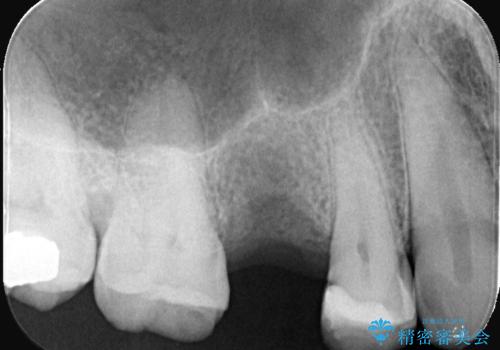

- 「歯茎にニキビみたいのが出来て歯が揺れている」を主訴に来院された患者様です。

右上5番が根尖性歯周炎と歯周病が同時に併発しており、骨が大きく溶け、歯の動揺も著しかったため保存困難と判断をし抜歯してインプラントで治療を行いました。

右上4番は虫歯になっていたので、虫歯を除去後、セラッミクインレーで治療を行いました。